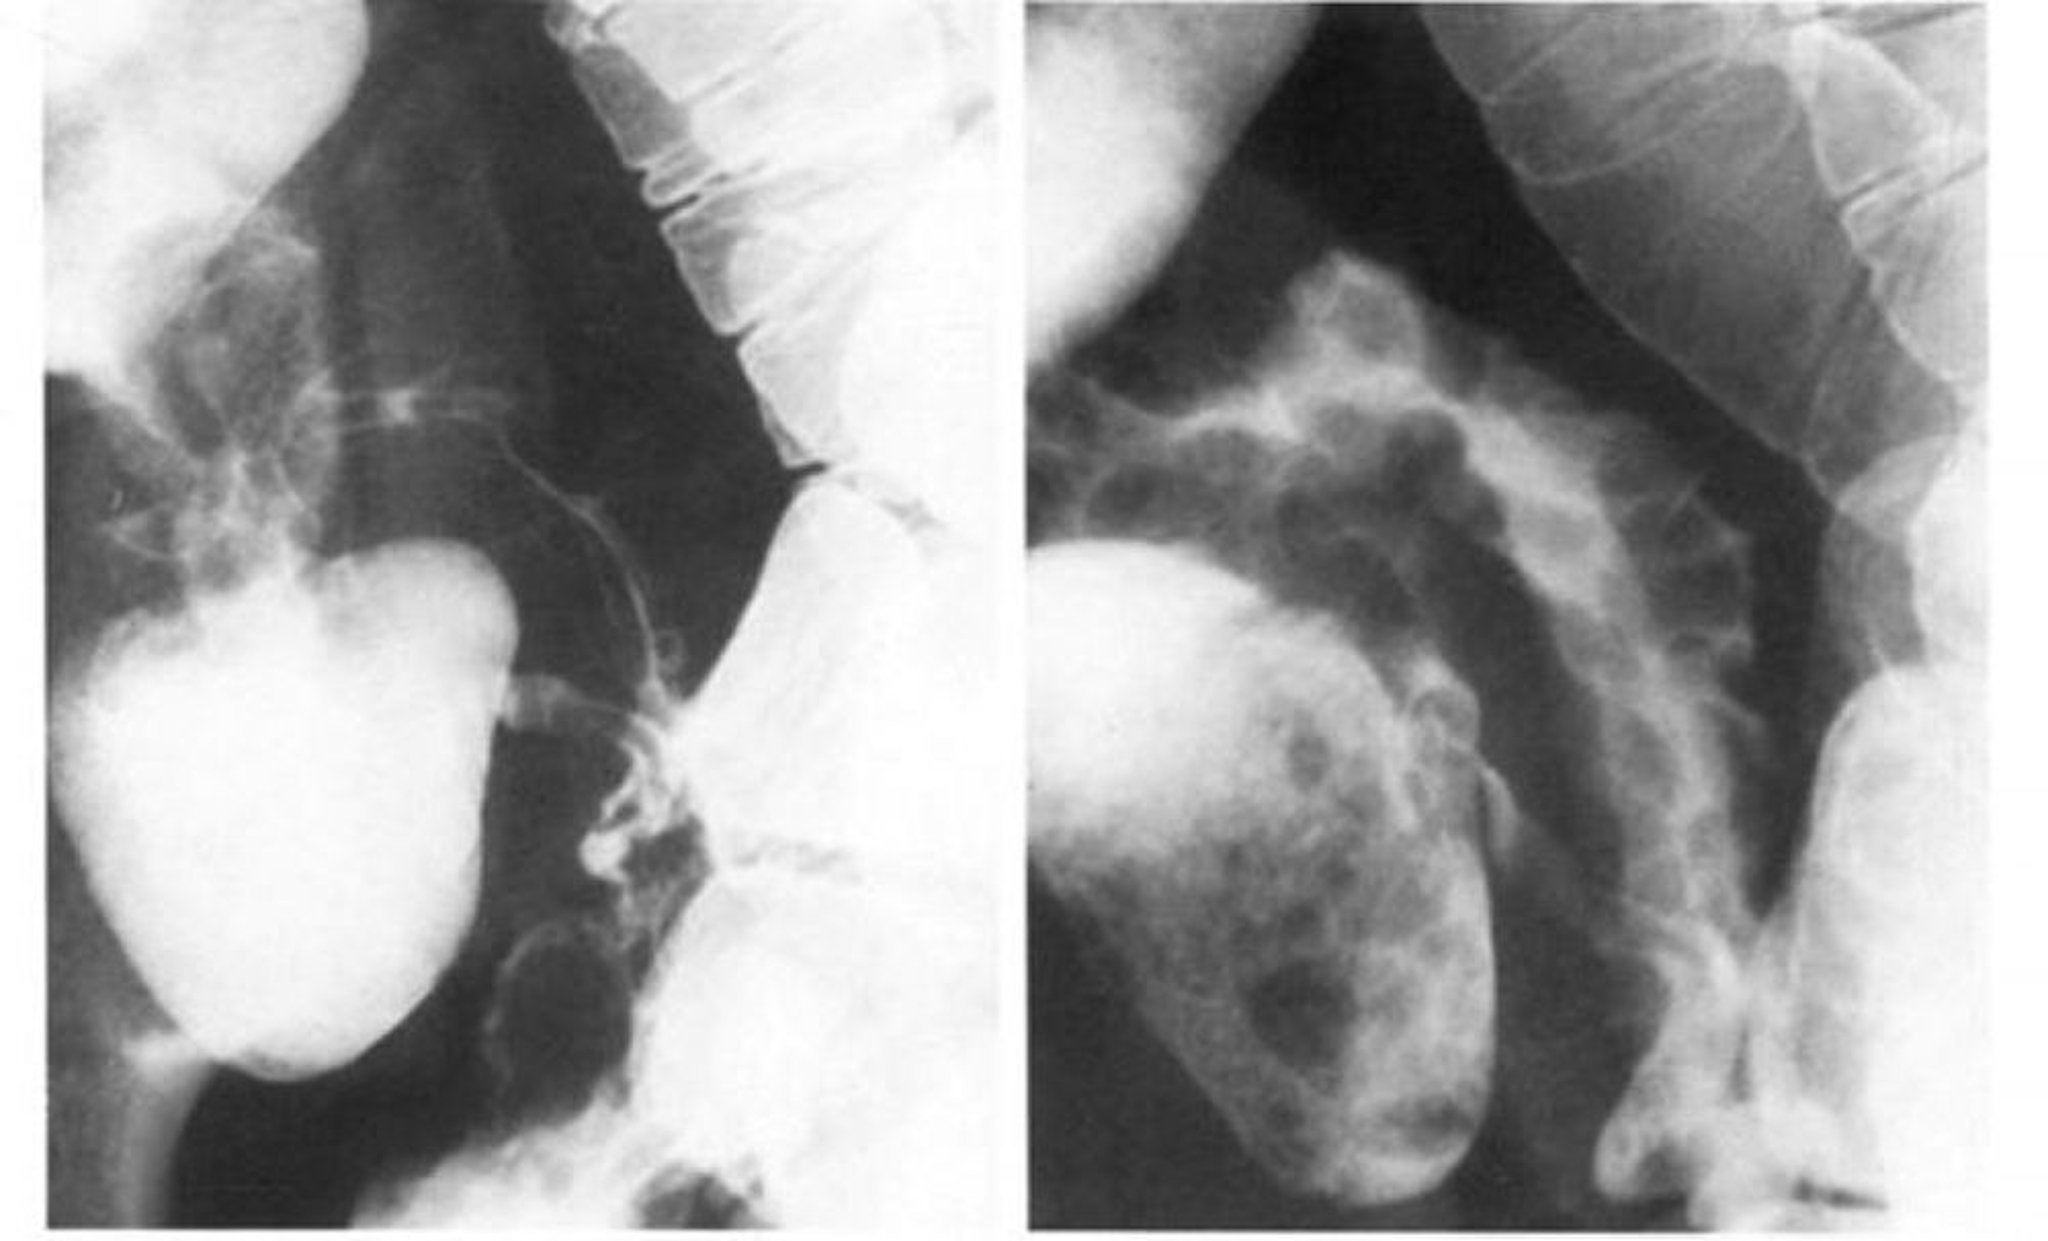

Transit de l'intestin grêle dans la maladie de Crohn montrant une sténose serrée

L'image de gauche montre le spasme oblitérant l'aspect pavé de l'iléon terminal, qui est mieux vu en double contraste sur l'image de droite.